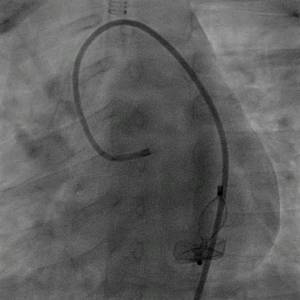

从右侧股动脉引入5F PDA鞘直至瘘口,经鞘管将12 mm的AMPLATZER Plug(AVP Ⅱ)1枚栓塞瘘口。

图片